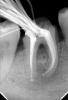

Михалыч007 Опубликовано 24 мая, 2012 Поделиться Опубликовано 24 мая, 2012 после 3 месяцев ведения зуба на кальцийсодержащих препаратов зуб запломбирован гуттаперчей( видно разницу в структуре костной ткани-она начала восстанавливаться) 1 Ссылка на комментарий

Михалыч007 Опубликовано 24 мая, 2012 Поделиться Опубликовано 24 мая, 2012 ещё одномоментная пломбировка зуба гуттаперчей Ссылка на комментарий